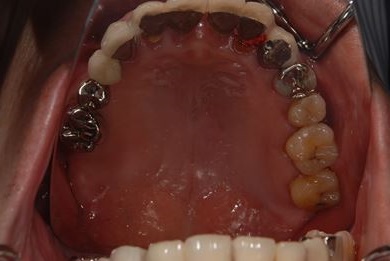

インプラントの症例写真 IMPLANT

骨再生スピードインプラント治療+セラミック治療

| 治療方針 | 上前歯部は、抜歯と同時にインプラントを埋入し、治療期間を短縮する。左上奥は、ソケットリフトにて上顎洞を拳上し、インプラント治療を可能にする。 | ||||||||||||||||||||||||||||||||

| 治療内容 | インプラント4本(ソケットリフト・抜歯即日)、テンポラリーインプラント2本、メタルボンドクラウン9本 | ||||||||||||||||||||||||||||||||